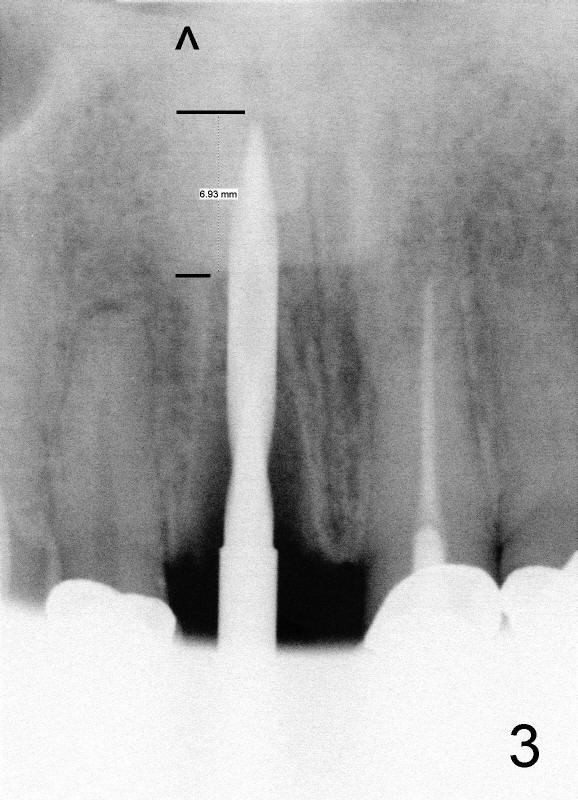

四十四岁女病人上颌中切牙突然断裂(图一:8),经过讨论,她同意植牙。由于根尖(图二黑线轮廓)上方骨头很多(箭头:鼻底),适合立刻植牙。牙根长度十一毫米左右,宽度约五毫米,准备植入直径五毫米植牙。拔牙后使用两毫米钻头,深度二十毫米(图三从颊侧牙龈缘算起),超过牙槽窝底部接近七毫米,所以植牙至少有七毫米新骨支持,将非常稳定。然后逐步使用2.5, 3.0, 和3.5毫米钻头,同一个深度,边钻边注意钻头(图四:D)近远中(图四)以及颊舌侧(图五)方向。